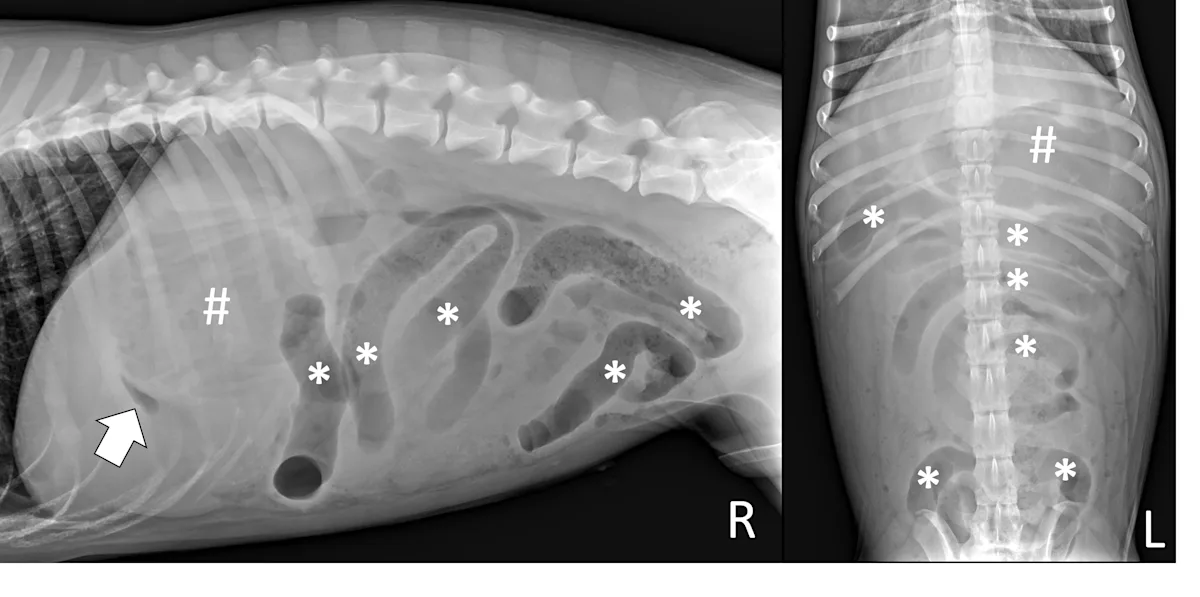

Small intestinal mechanical obstructions occur when a foreign body blocks the lumen of any segment of the small bowel, causing segmental dilation located orad to the foreign body. As the small bowel increases in size, it becomes crowded in the peritoneal space and begins stacking on itself with sharp, hairpin turns (Figure 4).1 Dilated portions of the small bowel usually contain a mixture of fluid and gas. Occasionally, intraluminal gas may outline part of a foreign body, making the object easier to see. Although the diameter of the small intestine can be objectively measured and compared with the height of the center of the L5 vertebral body,6,7 one study found that using the small intestinal diameter:vertebral body height ratio did not increase the diagnostic accuracy for mechanical obstruction on radiographs regardless of clinician experience.8

Right lateral and ventrodorsal abdominal radiographs of a 1-year-old neutered male domestic shorthair cat with a small intestinal mechanical obstruction from a surgically confirmed earplug lodged in the distal jejunum. The stomach is mildly dilated with fluid and gas (pound signs). Segmental fluid and gas dilation of the small bowel with stacking and hairpin turns can be seen (asterisks). On the ventrodorsal projection, intraluminal gas outlines the margin of the earplug (arrow).